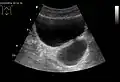

Bladder diverticula as seen on ultrasound with doppler[18]

Bladder diverticula as seen on ultrasound[18]